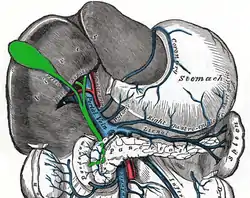

The splenic vein, here called the "lienal vein", travels from the spleen, above the pancreas, and ends in the portal vein. | |

In human anatomy, the splenic vein (formerly the lienal vein) is a blood vessel that drains blood from the spleen, the stomach fundus and part of the pancreas. It is part of the hepatic portal system.

The splenic vein is formed from small venules that leave the spleen. It travels above the pancreas, alongside the splenic artery. It collects branches from the stomach and pancreas, and most notably from the large intestine (also drained by the superior mesenteric vein) via the inferior mesenteric vein, which drains in the splenic vein shortly before the origin of the hepatic portal vein. The splenic vein ends in the portal vein, formed when the splenic vein joins the superior mesenteric vein.